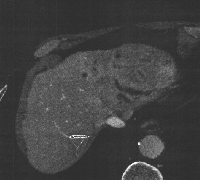

Πρόκειται για άνδρα ασθενή 70 ετών ο οποίος, στα πλαίσια διερεύνησης καθημερινών εμπύρετων επεισοδίων, διαπιστώθηκε ότι έπασχε από πολλαπλά αποστημάτια του αριστερού ηπατικού λοβού, ως συνέπεια ηπατικής λιθίασης (εικόνα 1). Επιπλέον, ο ασθενής παρουσίαζε στένωση στο διχασμό του κοινού ηπατικού πόρου (εικόνα 2) και θρόμβωση του αριστερού κλάδου της πυλαίας φλέβας. Αν και η ύπαρξη κακοήθειας δεν επιβεβαιώθηκε ιστολογικά, η ανάπτυξη χολαγγειοκαρκινώματος δεν μπορούσε να αποκλεισθεί προεγχειρητικά και έτσι ο ασθενής υποβλήθηκε σε εκτομή του χοληδόχου πόρου με λεμφαδενικό καθαρισμό (εικόνα 3) και αριστερή ηπατεκτομή με τον κερκοφόρο λοβό (εικόνα 4). Η αποκατάσταση του χοληφόρου δέντρου πραγματοποιήθηκε με τελικο-τελική ηπατικο-νηστιδική αναστόμωση (εικόνα 5) με τη χρήση οπισθοκολικής έλικας μήκους 70 cm κατά Roux en Y (εικόνα 6). Έκτοτε, ο ασθενής είναι ελεύθερος εμπύρετων επεισοδίων.